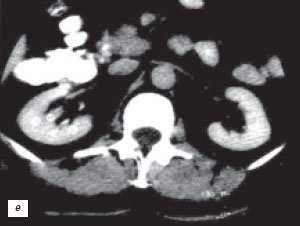

• КТ с контрастированием:

о Отсутствие объемного образования

о Контрастирование аналогично нормальному корковому веществу:

- Лучшая визуализация в кортико-медуллярную фазу

- При недостаточной информативности аксиальной проекции эффективна коронарная реконструкция

(Справа) КТ, аксиальная проекция, кортико-медуллярная фаза контрастирования: дорсальная половина межполюсной области почки, контрастируемая аналогично корковому веществу почки. На последующих фазах выявлено гомогенное контрастирование почки.

(Справа) КТ с контрастированием, аксиальная проекция: у этого же пациента установлено, что «объемное образование» — это нормальное корковое вещество почки, которое инвагинирует в почечную лоханку между чашечками верхнего полюса и меж полюсной областью почки. Обратите внимание на нормальный внешний контур почки. Бертиниевы колонны чаще всего выявляют с одной стороны и слева, как в данном случае: в 18% случаев они могут быть двусторонними.